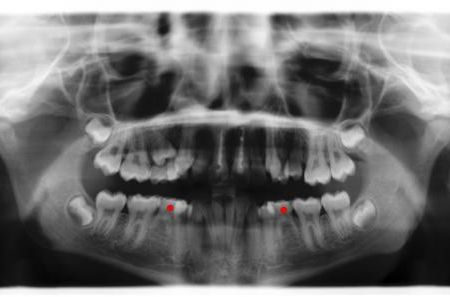

Röntgenbefund

Vor und nach der Behandlung

Die roten Punkte auf der linken Röntgenaufnahme markieren die Milchbackenzähne ohne Nachfolger, die ausgleichend enfernt wurden. Auf der rechten Aufnahme sieht man die Situation nach dem Lückenschluß.